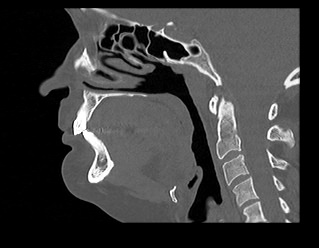

Одним из методов диагностики заболеваний носоглоточной области является мультиспиральная компьютерная томография. КТ носоглотки назначают при подозрении на рост новообразований, в случае хронического воспаления, при врожденных аномалиях строения носа и прилегающих к нему придаточных пазух.

Методика предусматривает использование рентгеновского излучения. Благодаря различной способности тканей поглощать рентгеновские лучи и последующей цифровой обработке полученных данных, удается получить изображения исследуемой зоны в мельчайших подробностях.

В медицинских центрах «Доступная медицина» сканирование носоглотки выполняется на современных мультиспиральных компьютерных томографах экспертного класса TOSHIBA AQUILION. Модификации данных аппаратов снабжены увеличенным количеством высокочувствительных детекторов, которые производят послойное сканирование, делая одномоментно от 64 до 128 срезов анатомической зоны. Это позволяет проводить исследование за несколько секунд. Такая быстрота выполнения исследования обеспечивает минимальную дозу рентгеновского облучения для пациента.

Инновационные цифровые приложения томографов позволяют получить снимки высокого качества и детализации, а также создать трехмерные реконструкции анатомической зоны исследования, что дает возможность рассмотреть пространственное расположение органов и патологических образований.